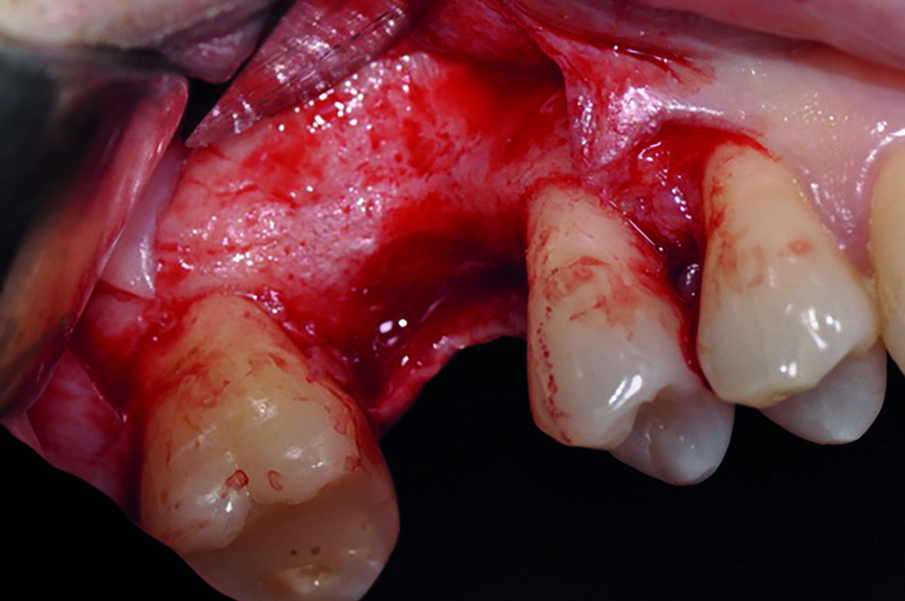

Il passaggio successivo consiste nell’elevare tale membrana, arrivando a scollare sino alla porzione più interna del seno mascellare (lato palatino), ottenendo una membrana senza tensioni e possibilmente senza lacerazioni (Fig. 3). Una volta elevata la membrana si procede con i passaggi di frese per creare il neo alveolo nella porzione di osso nativo.